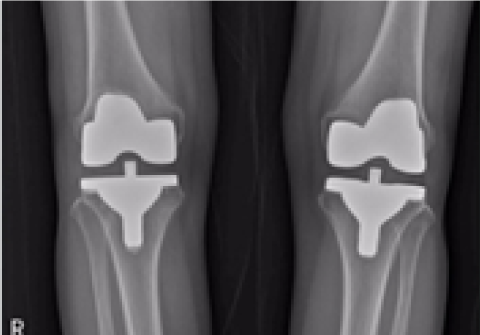

무릎 인공관절 부분치환술

2016.06.27

2016.12.28